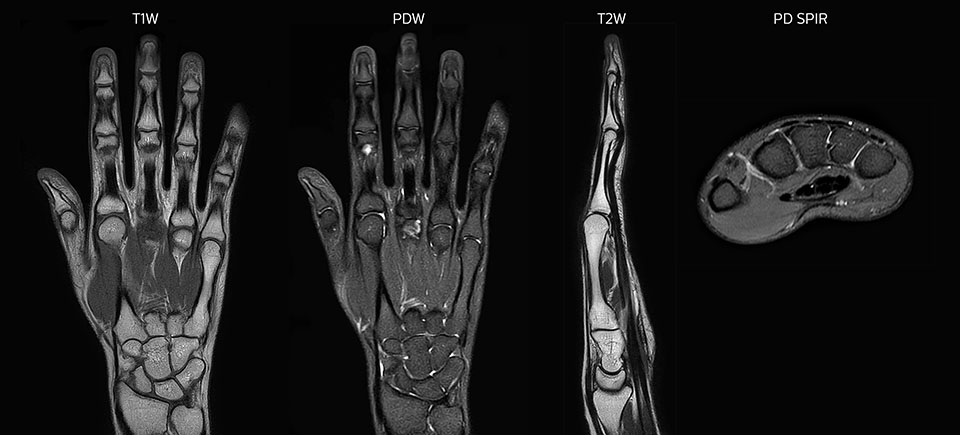

Clinical cases from Radiology Schiffer

MRI of hand and wrist with large FOV

Prodiva imaging of the hand covers the fingertips and includes the full wrist as well. The dS MSK M coil is easy to use.